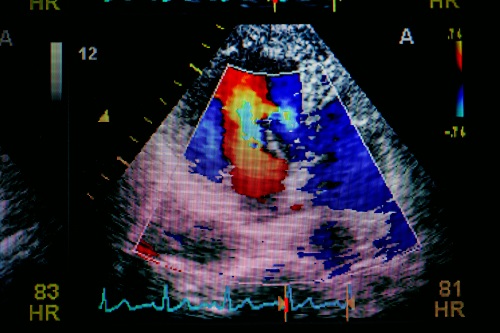

2. 心臟超聲波(Echocardiography)

心臟超聲波檢查利用高頻率聲波作多方位及多角度心臟掃描,獲得即時影像,用以評估心臟結構及功能是否正常,例如心瓣膜是否正常運作、心臟收縮、跳動及泵血等情況都一目了然。檢查簡單、非創傷性,也沒有輻射,因此,心臟超聲波是最常用的非入侵性心臟影像檢查。